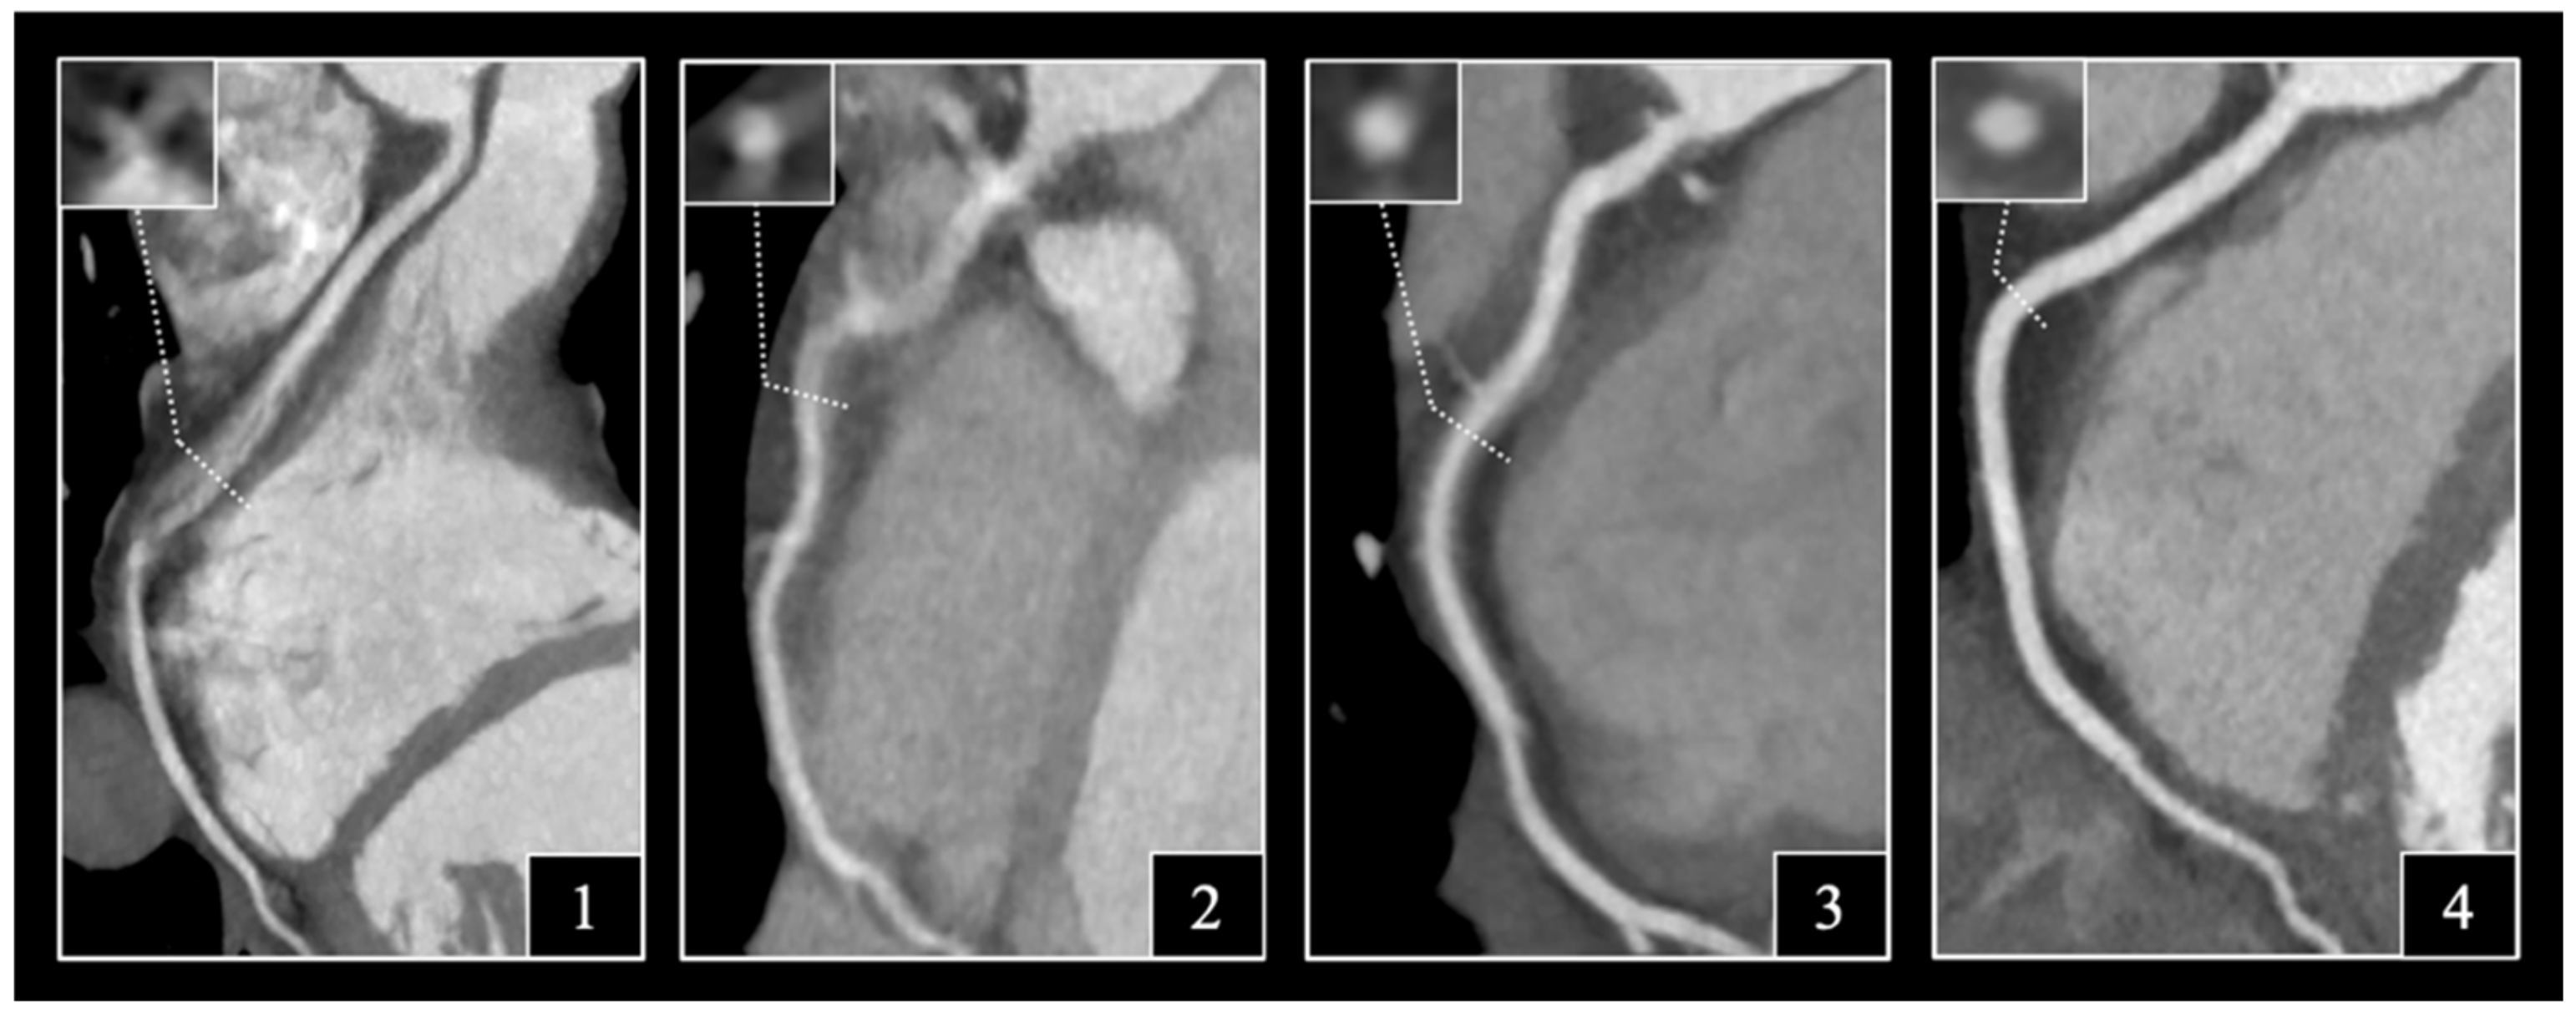

2.4. Assessment of Image Quality

3.3. Image Interpretability

3.4. Subjective Image Quality on Per-Patient, Per-Vessel and Per-Segment Levels